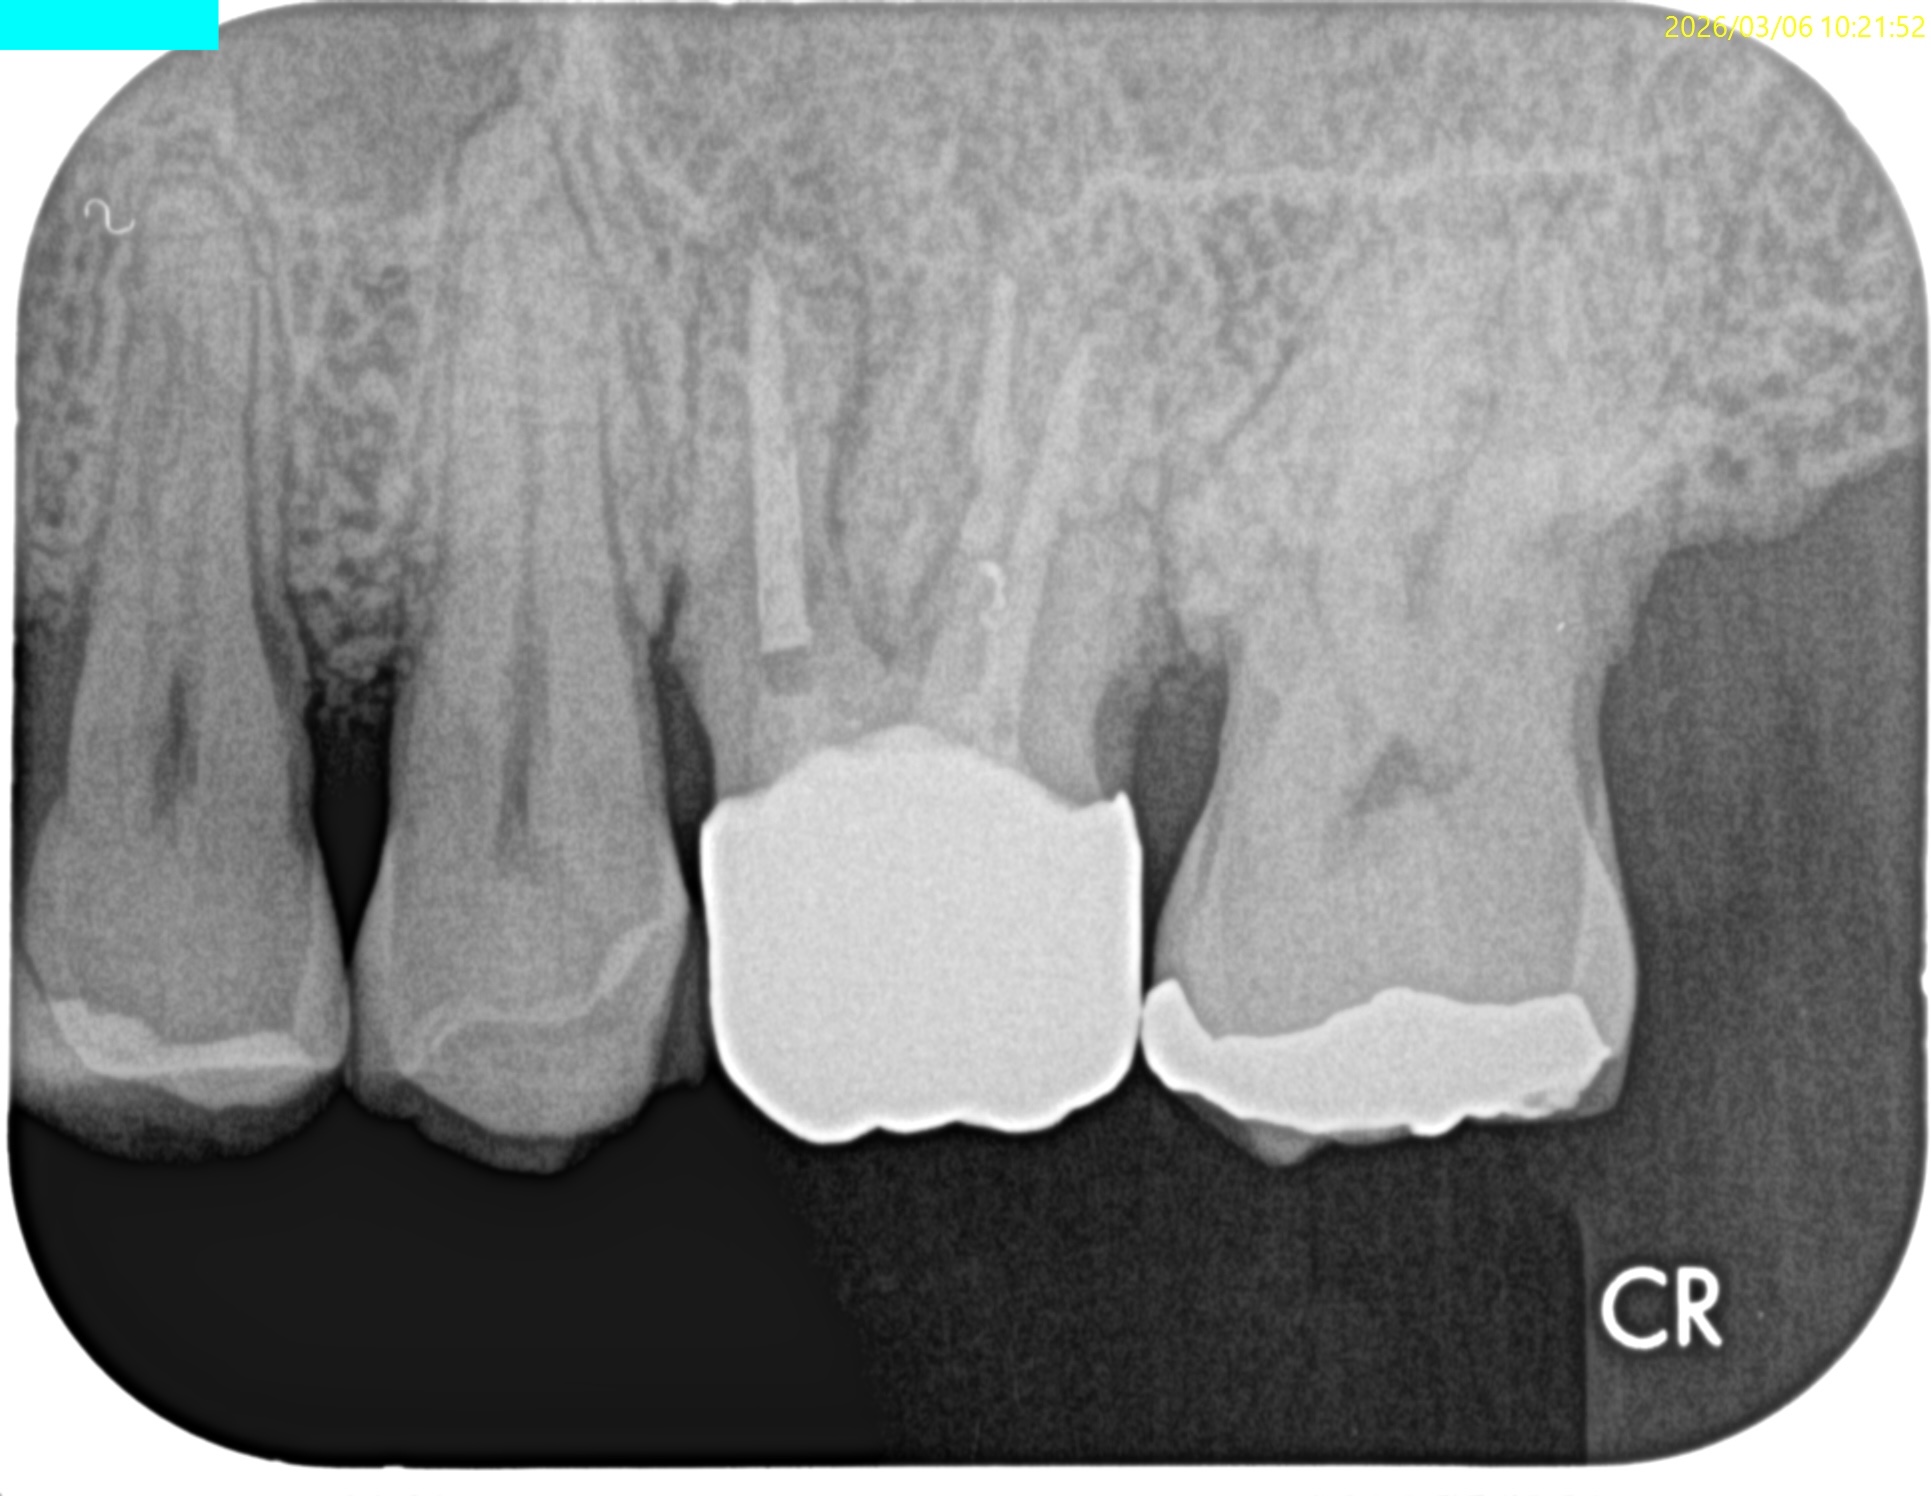

Pre-op Endo Test(2026.3.6)

MBの根尖病変が大きくなり上顎洞に穿孔している。

歯性上顎洞炎の可能性がある。

そしてMB2と思しきものはあるが、それが非外科的歯内療法で穿通する保証もない。